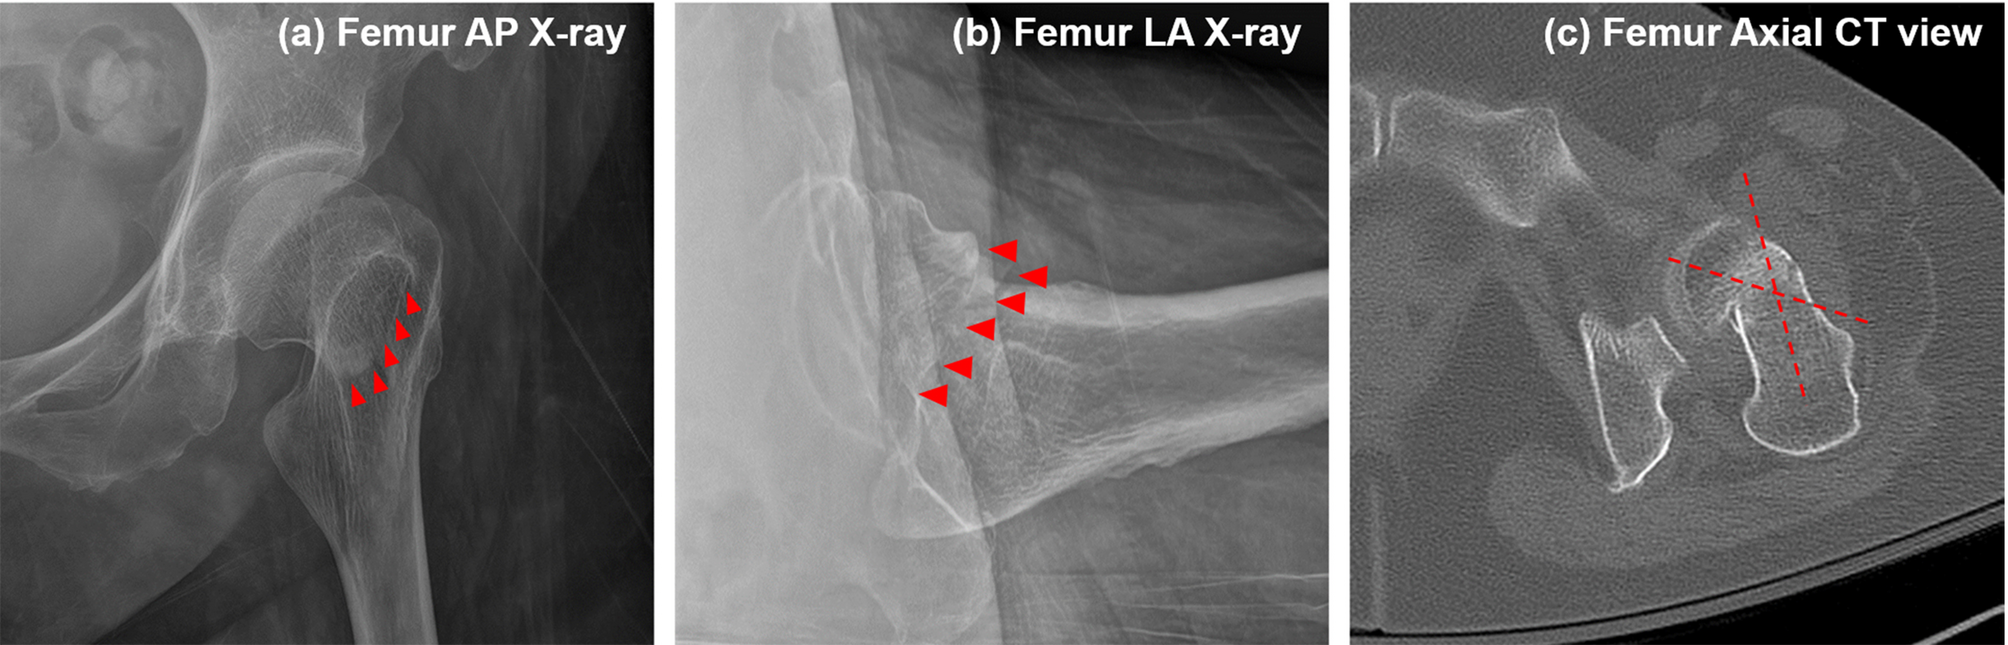

Example for misclassification of femoral neck fractures in X-ray images. Images of a 69-year-old female patient are presented: (a) X-ray anteroposterior (AP) view, (b) X-ray lateral (LA) view, and (c) axial computed tomography (CT) scan. The ensemble model classified the fracture as Garden type IV based on X-ray images of the AP and LA views. However, CT scan evaluation showed the fracture to be Garden type III due to posterior angulation.